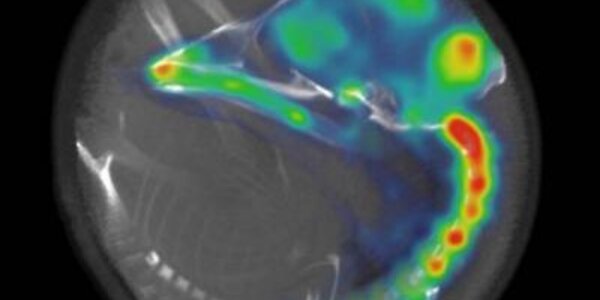

Embryo Brains Can Wake Earlier Than Previously Thought

A new imaging study shows the brains of embryonic chicks can 'wake' long before chicks are ready to hatch out of their eggs - but it took loud, meaningful sounds. Playing meaningless sounds wasn't enough to rouse their brains. As modern medicine continues to push back the gestational age at which prematurely born infants can reliably survive, pediatricians have worried about the effects of stimulating brains that are still 'under construction'. It turns out that,like adult brains, embryo brains also have neural circuitry that monitors the environment to selectively wake the brain up during…